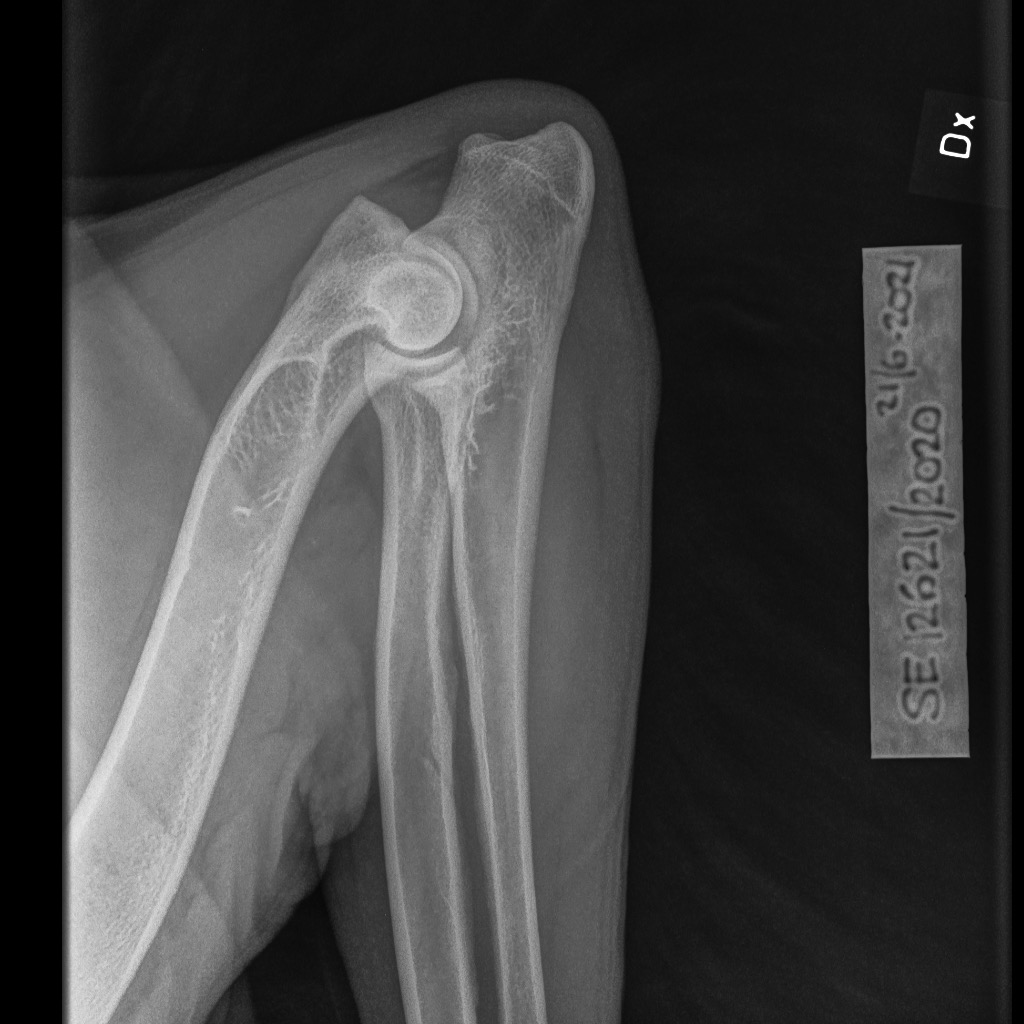

Men för alla experter där ute, så här ser den armbåge ut som enligt avläsaren har en pålagring. Kan du se var den 1:an sitter så får du gärna visa och kommentera.